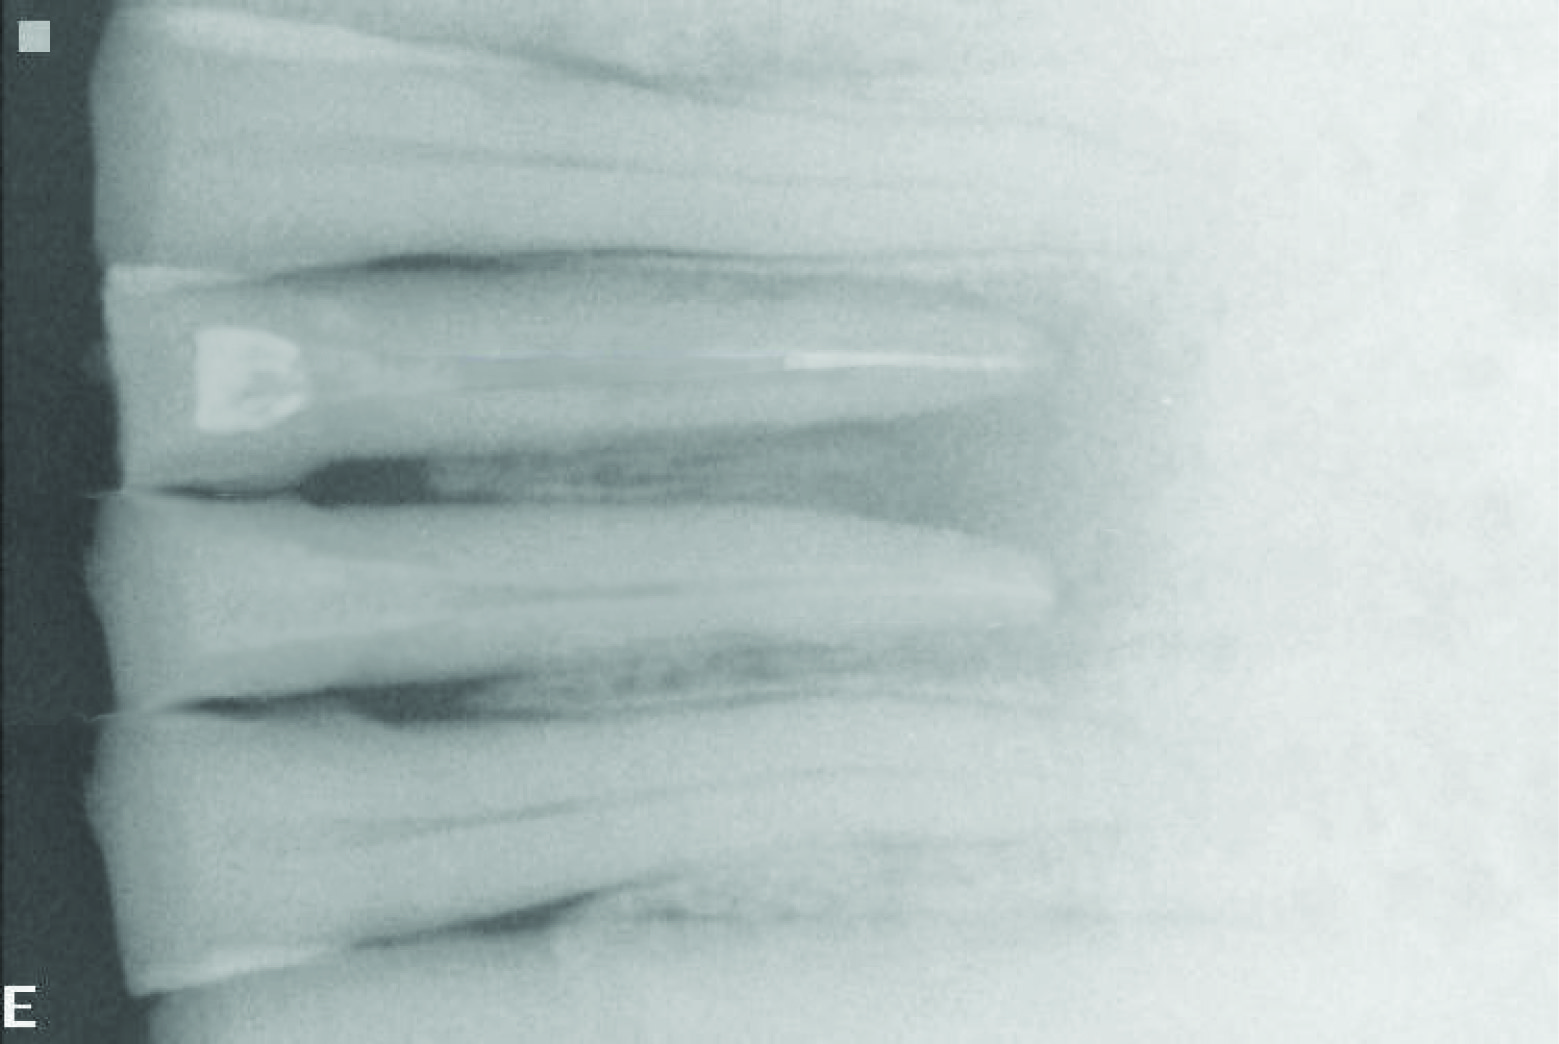

A 12-year-old female patient visited the Department of Pediatric Dentistry with a complain of broken left lower front tooth since four months. The patient did not complain of any pain [Table/Fig-1]. The parent of the patient told that the girl had a fall two years back in which the lower front tooth got broken. There was pain and tenderness reported at that time and they had visited a dentist for the same. On further enquiry it was revealed that the mentioned tooth had been root canal treated six months back and restored but the restoration came out within a month. The re-restoration also did not last more than 15 days. On examination lower left central incisor was fractured and there was neither pain reported nor tenderness to percussion. The tooth structure was less for a composite make-up or a crown. After thorough examination it was decided to go for a post and core and composite make up. As it was an anterior tooth in a young patient it was decided to go for fibre-reinforced composite (Ribbond, Ribbond THM, Ribbond inc.Seattle,WA) as post and core material as it is esthetic and has adequate strength. As the tooth was adequately obturated [Table/Fig-2], preparation of the canal space was done [Table/Fig-3,4]. The use of ribbond does not require additional tooth preparation as is required for metal posts. The remaining tooth structure being less, rubber dam isolation could not be accomplished and we decided for high suction evacuation with cotton rolls to be suitable for isolation. Gutta percha was removed using gutta percha solvent until the desired length for post was achieved. The post hole was shaped using Gates Glidden drills (Roydent, West Palm Beach, FL), cleaned with 5% sodium hypochlorite and dried. The width of Ribbond is to be decided on the root canal space available. The depth of the post space was measured using a periodontal probe, and a 3-mm-wide Ribbond was cut using special scissors provided with the kit (Ribbond starter kit, Ribbond THM, Seattle), measuring twice the depth of the post space and 3–4 times the height of the core build-up [Table/Fig-5] and placed in dual cure adhesive resin and set aside in light protected container. The root canal wall was etched, washed thoroughly and then air-dried gently. Excess water was removed from the post space using paper points . The dual cure adhesive resin (Ed Primer II A&B) was applied using a microbrush and gently air-dried to evaporate the solvent. Dual cure resin cement was then placed inside the canal space. The Ribbond was removed from the resin and the excess resin was removed using a hand instrument [Table/Fig-6], folded in a V-shape and coated with dual-curing resin cement (Panavia, Kuraray Medical Inc., Japan). The piece of ribbond was then placed in the post space in a labial-lingual direction with a periodontal probe [Table/Fig-7]. Excess resin cement was removed, and the cement was cured for 20 s. The two protruding ends of the Ribbond strips formed the reinforcement for the core build up to replace the lost coronal portion of the tooth. The remaining resin mix from the syringe was extruded onto this framework to create a core resembling almost like the shape of a lower central incisor. The space between the protruding ribbon ends was filled with resin so as not to leave any voids. Composite resin was also placed so as to cover the ribbon ends completely and leave none of them exposed on the outer surface of the core. All the material was thoroughly light cured to create a set surface. The material was left in the mouth for a couple of hours to ensure complete set of the self curing component of the resin mix. The result of this procedure came out to be a single piece post and core, which was bonded onto the root, creating a solid structure without any wedging effect on the root. Moreover, the resin conforming to the inside shape of the canal space ensured no voids and eliminated “fitting” problems normally associated with cast posts. The bands of Ribbond reinforced the resin material and made it extremely strong and durable. Bonding of the entire material also created a single block of post and core, which is the essence sought for favourable occlusal force transmission and for resistance against debonding of the entire unit. The best thing was, there was no metal to mask with the crown since the base shade of the composite was a close enough match to the tooth and was translucent. These strips, although opaque, were white in colour and after being completely encased in the composite, were not visible. However, they did not contribute to the colour of the core in any adverse way. The restorative procedure was completed by building up the tooth using dual cure hybrid composite resin following technique of small progressive build up without any matrix [Table/Fig-8,9]. All these increments were fully light cured. Finishing and polishing procedures were performed using composite contouring and polishing discs. The patient was advised for a crown at a later stage after complete development of occlusion. The patient has been under follow up for two years now with six month follow up intervals and the restoration is still in good condition [Table/Fig-10,11]. As because the occlusion is not yet established we have decided to give crown on a later date.

Radiograph showing good obturation